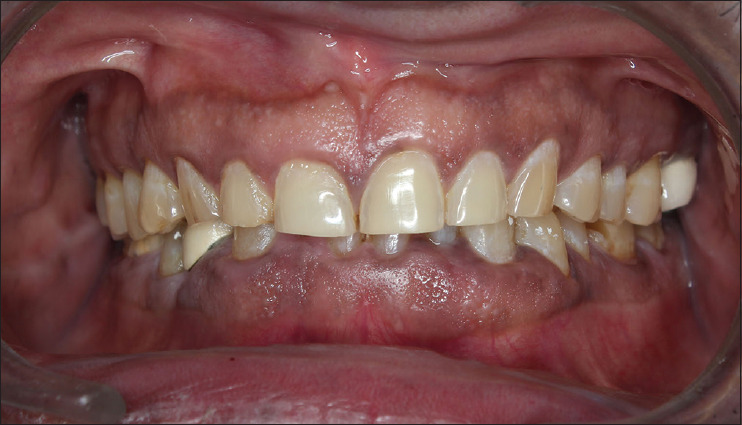

Prosthetic rehabilitation in multifaceted dental abnormality needs sequential planning to ensure adaptation of oral and associated musculature. Reduction of tooth structure before adaptation of oral and associated components may complicate the treatment modality if compliance of the musculature is poor. Hence, the fabrication of over-provisional in esthetic rehabilitation enables to assess of the success of the treatment plan preoperatively before invasive trials. A 55-year-old male with a diagnosis of Category I loss of vertical dimension, according to Turner and Missirlian classification, required full mouth rehabilitation. The case report depicts the preoperative management of full mouth rehabilitation with direct chair-side technique using over-provisional to analyze the esthetic and functional changes. Restoration of esthetics is a complex task that needs patient satisfaction to achieve success. Over-provisional is a simplified method of establishing esthetics and functional rehabilitation. Esthetic and functional rehabilitation of an individual can be an easy transition when preoperative evaluation of the final prosthesis design is visually created intraorally.